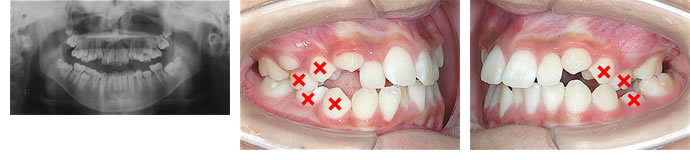

左上臼歯が舌側に傾斜し、左下臼歯が頬側に傾斜して交叉咬合(歯列の一部の咬み合わせが前後逆になっている状態)となっていました。

下顎のずれを改善するために、上顎は左右の第一小臼歯(4番)と第二乳臼歯(E)を、下顎右側は4番・Eの2本、左側は第二小臼歯(5番)のみという非対称的な抜歯を行い(×印)、スタンダードエッジワイズ法で治療を開始しました。

偏位咬合の治療は、歯列弓(アーチフォーム)の調節や臼歯部の左右のねじれ(トルク)調節を自在に行う必要があるため、ワイヤーの屈曲を行うスタンダードエッジワイズ法が適していると考えます。